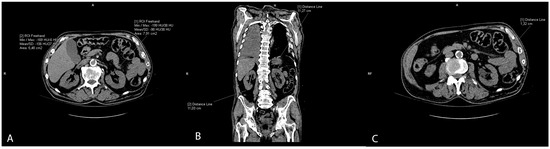

2.5. Renal Sinus Fat Accumulation and Renal Imaging Parameters

The slices of the renal hilus of each kidney containing the largest amount of sinus fat were used to measure a renal sinus fat area in cm2, representing ectopic renal sinus fat accumulation. The sinus fat surface area was traced manually and identified by its low-density fatty content with a negative HU (Figure 3A). The length of the kidney was measured on the coronal reconstructions as the longest craniocaudal diameter of each kidney (Figure 3B). Renal parenchymal thickness was measured at the hilar level on axial scans (Figure 3C).

Figure 3. Representative CT scans showing renal parameter volume measurements: renal sinus fat area (A), length of the kidney (B), and renal parenchymal thickness (C).